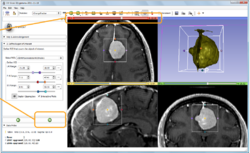

Image Phenotyping

• Based on: 3D Slicer version 4.10

• The Image Phenotyping tutorial is an introduction to brain tumor segmentation and image phenotyping using the Slicer Radiomics extension.

• Authors: Sonia Pujol, Ph.D.

• Audience: Clinical researchers

• Dataset: Meningioma dataset